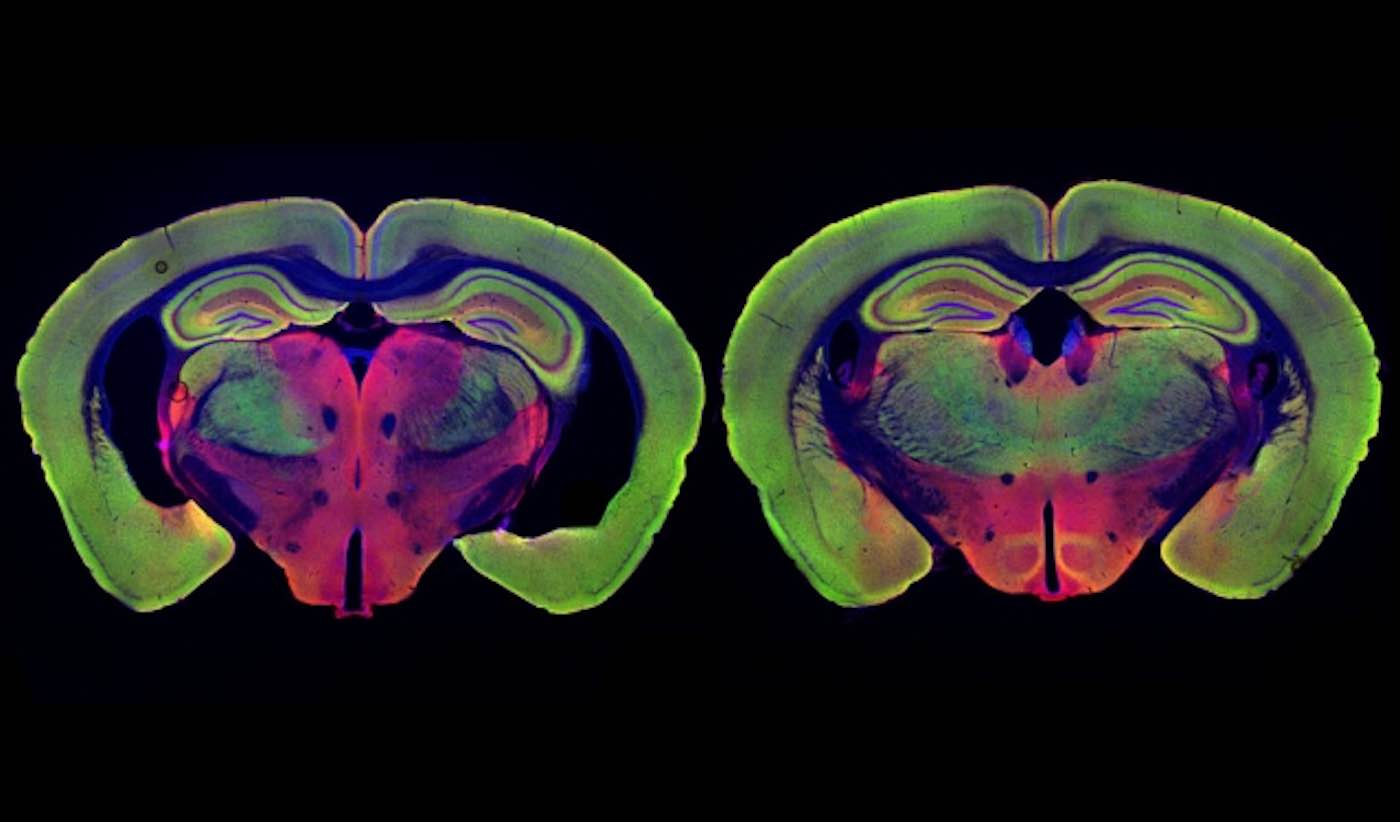

Photo by Chinnakkaruppan Adaikkan / MIT News

In their new study, the researchers wanted to delve deeper into how these beneficial effects arise. They focused on two different strains of mice that are genetically programmed to develop Alzheimer’s symptoms. One, known as Tau P301S, has a mutated version of the Tau protein, which forms neurofibrillary tangles like those seen in Alzheimer’s patients. The other, known as CK-p25, can be induced to produce a protein called p25, which causes severe neurodegeneration. Both of these models show much greater neuron loss than the model they used for the original light flickering study, Tsai says.

The researchers found that visual stimulation, given one hour a day for three to six weeks, had dramatic effects on neuron degeneration. They started the treatments shortly before degeneration would have been expected to begin, in both types of Alzheimer’s models. After three weeks of treatment, Tau P301S mice showed no neuronal degeneration, while the untreated Tau P301S mice had lost 15 to 20 percent of their neurons. Neurodegeneration was also prevented in the CK-p25 mice, which were treated for six weeks.